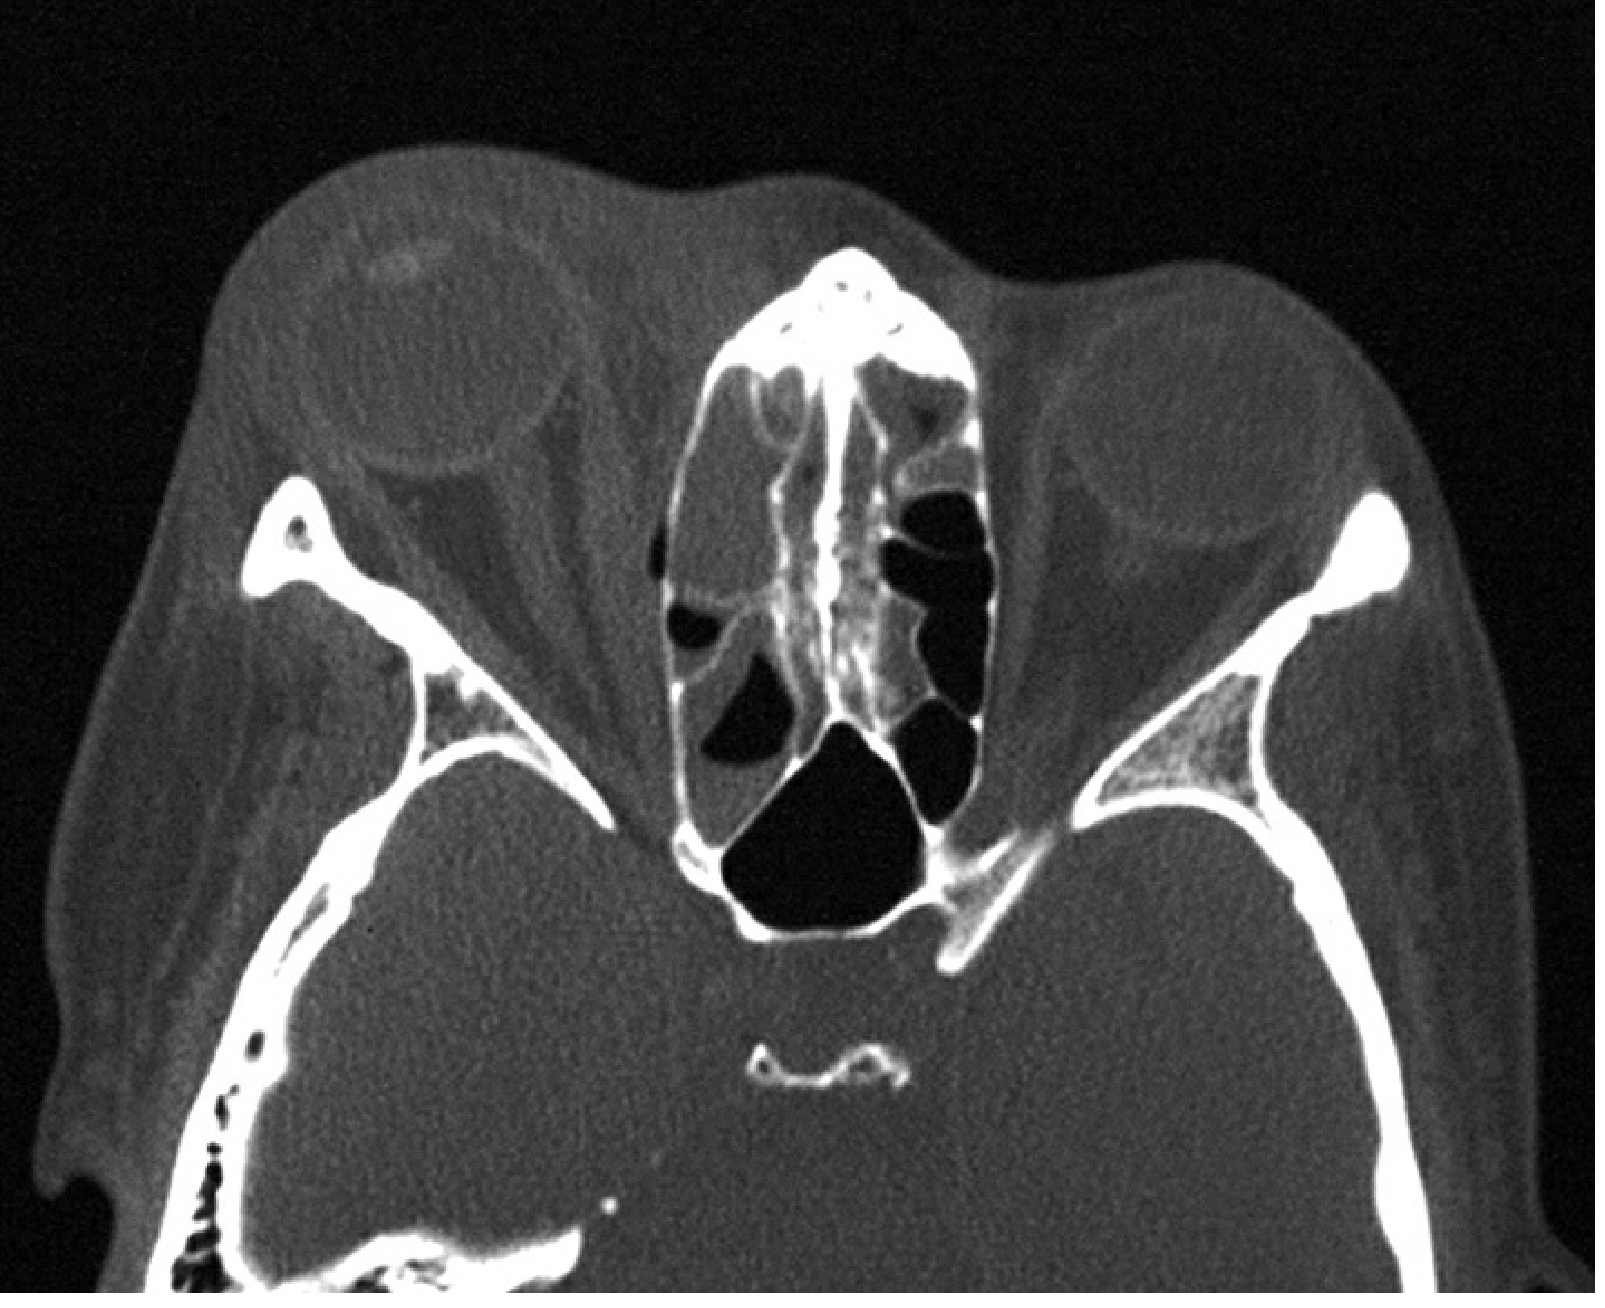

1. CT scan (orbits + paranasal sinuses + brain, with contrast) — vital: confirms diagnosis, identifies subperiosteal abscess (SPA), intracranial extension, or retained foreign body

CT of right orbital cellulitis showing fat stranding and right ethmoiditis

Axial CT showing right orbital fat stranding with ethmoiditis — Wills Eye Manual